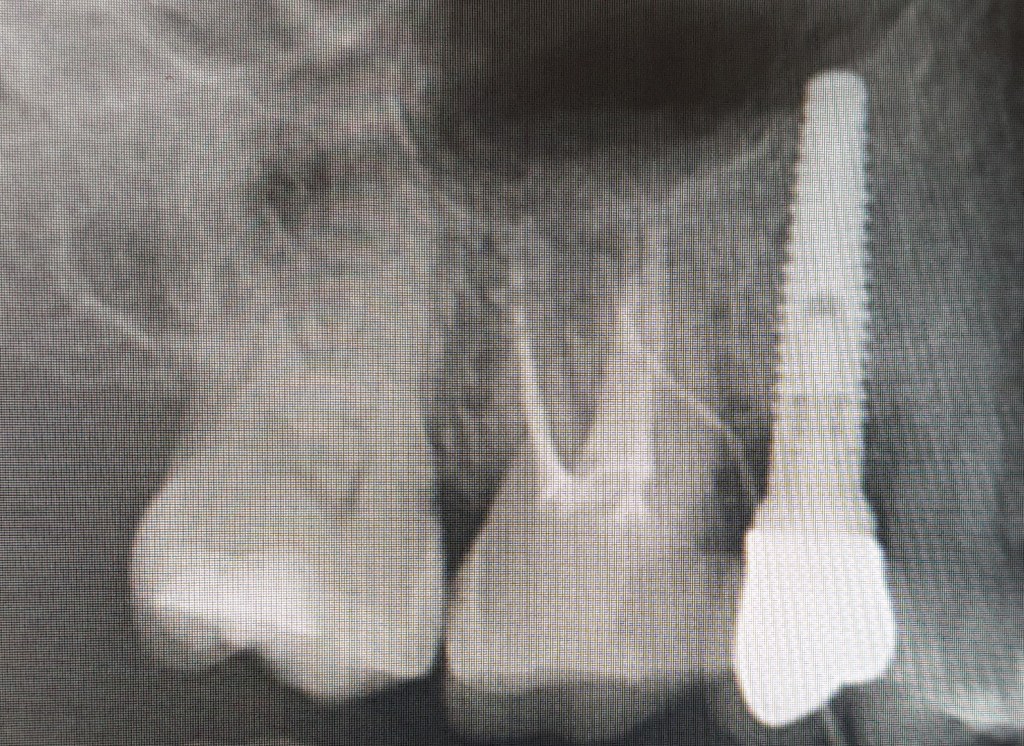

A panaszokat okozó fog megtalálása alapos szájvizsgálat és 2D röntgen segítségével sem mindig egyszerű.

Alapesetben a gyulladt fog (1) hidegre, melegre a megszokottól eltérő, erősebb érzékenységet mutathat. Jellemző lehet továbbá, hogy (2) ráharapásra, vagy kopogtatásra fájdalmat okoz. A gyulladás folyamatának előrehaladtával a fogról készült egyszerű kisröntgen is árulkodó lehet, mivel a gyökércsatorna vége felé haladó gyulladás a (3) gyökércsúcs körül jellegzetes radiodenz(sötét) foltot tehet láthatóvá.

Az alábbi eset a fogászati CT vizsgálat jelentőségét mutatja be.

Biztos, hogy az implantátummal van gond? Biztosan az felelős a gyulladásért?

Az ellentmondások miatt kis CT felvétel készítése mellett döntünk.